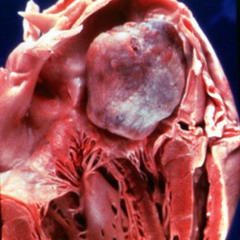

По внешнему виду миксома сердца представляет собой образование в виде полипа с желеобразным содержимым. Данная опухоль располагается на предсердной перегородке и в размерах достигает до 12-15 см.

В основном, миксома предсердия располагается в левой части, где получает кровь от легких. Опухоль может располагаться возле митрального клапана и препятствовать току крови из предсердия в желудочек. Периодически миксома то раскрывает, то закрывает отверстие клапана, нарушая кровоток.